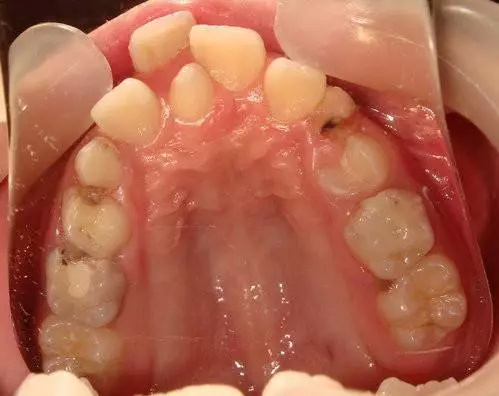

上前牙多生牙修复,各位指点一二 [病例帖]

男孩,9岁,常规检查时发现有多生牙存在,寻求拔除 有家族史,父亲以前中